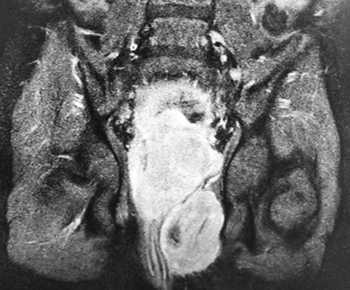

Обследование: ОАК (анемия умеренной степени, СОЭ 21 мм/ч); ОАМ (эритроциты, лейкоциты в большом количестве, белок 0,29, бактерии); БАК: Д-димеры 401 мкг/мл; ликвор (глюкоза 5,8); КТ головного мозга: гиподенсивный участок в левой теменно-затылочной зоне — участок ишемии (?); МРТ ГМ: мультифокальные билатеральные участки гиперинтенсивности в бассейне кровоснабжения сосудов задней циркуляции. (МР-картина может соответствовать синдрому задней обратимой энцефалопатии, васкулиту, эмболическим инфарктам мозга различной степени давности (?)); УЗИ ОБП: гидронефроз с обеих сторон, гиперплазия лимфоузлов; УЗИ мочевого пузыря: весь мочевой пузырь заполнен неоднородными массами, без признаков кровотока, в толще этих масс лоцируется катетер, жидкостной компонент не прослеживается (см. рис. 1); УЗИ БЦА: без патологии; ЭхоКГ: без патологии.

Рисунок 1. Результаты УЗИ мочевого пузыря.